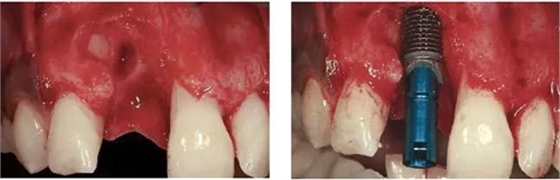

圖3、拔牙后看到更大范圍的骨缺損,并且缺損導致上頜側切牙根尖牙骨質暴露,繼而存在術后由于軟硬組織退縮而帶來的美學風險。

圖4、植入的種植體,初始穩(wěn)定性很好,由于骨缺損范圍大,選擇潛入式愈合。

圖5、種植體完全位于拔牙窩骨壁包圍的范圍內,距離唇側骨板至少2mm。